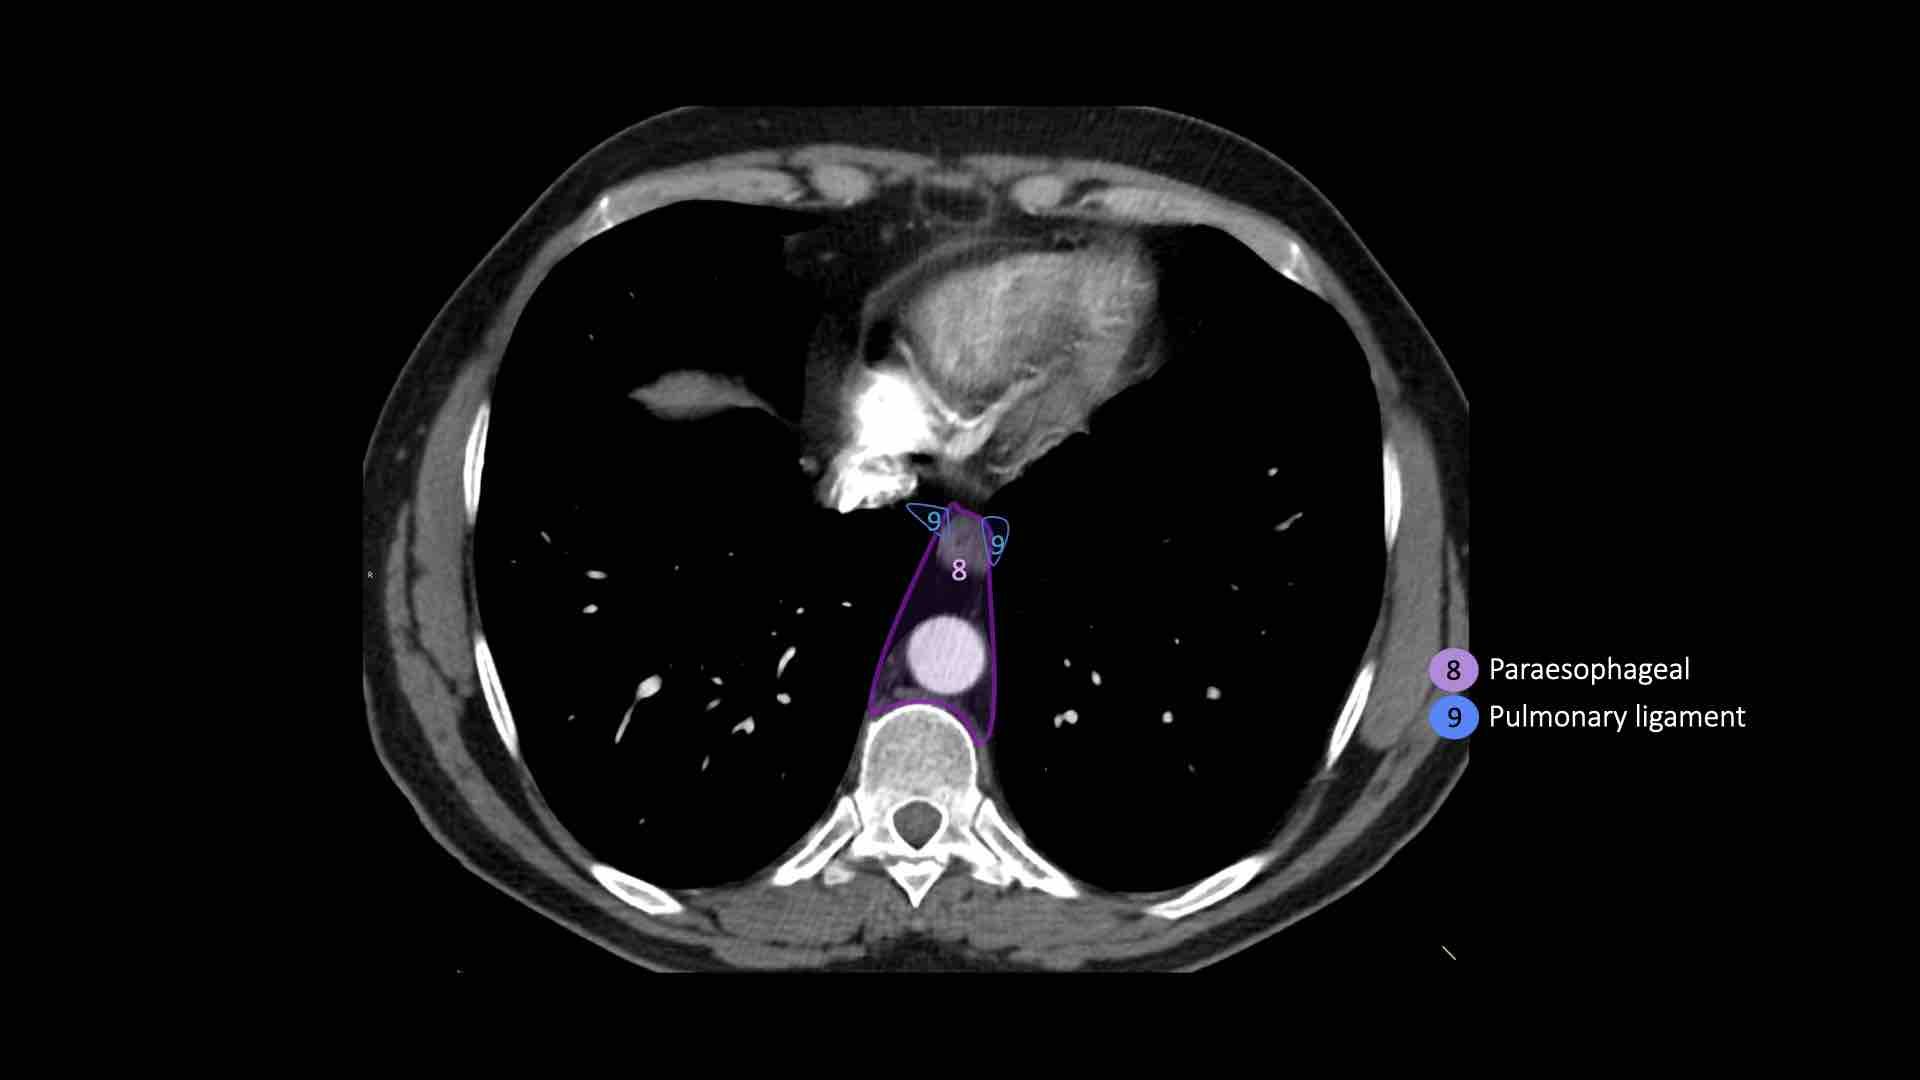

8. Cạnh thực quản

Các hạch nằm dưới carina.

9. Dây chằng phổi

Các hạch nằm trong dây chằng phổi.

8. Hạch cạnh thực quản

Các hạch này nằm bên dưới các hạch dưới carina và trải dài xuống đến cơ hoành.

9. Hạch dây chằng phổi

Hạch dây chằng phổi nằm trong dây chằng phổi, bao gồm các hạch ở thành sau và phần dưới của tĩnh mạch phổi dưới.

Dây chằng phổi là phần kéo dài xuống dưới của các nếp gấp màng phổi trung thất bao quanh rốn phổi.